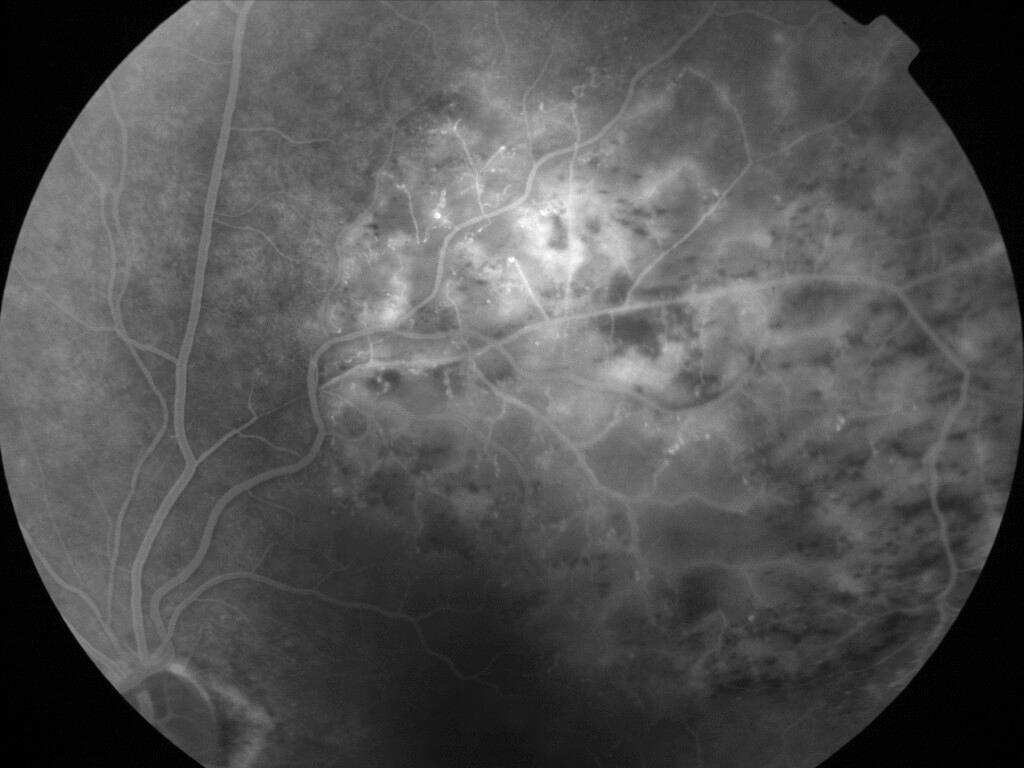

OCCLUSION DE BRANCHE DE LA VTS DE FORME ISCHEMIQUE MAJEURE